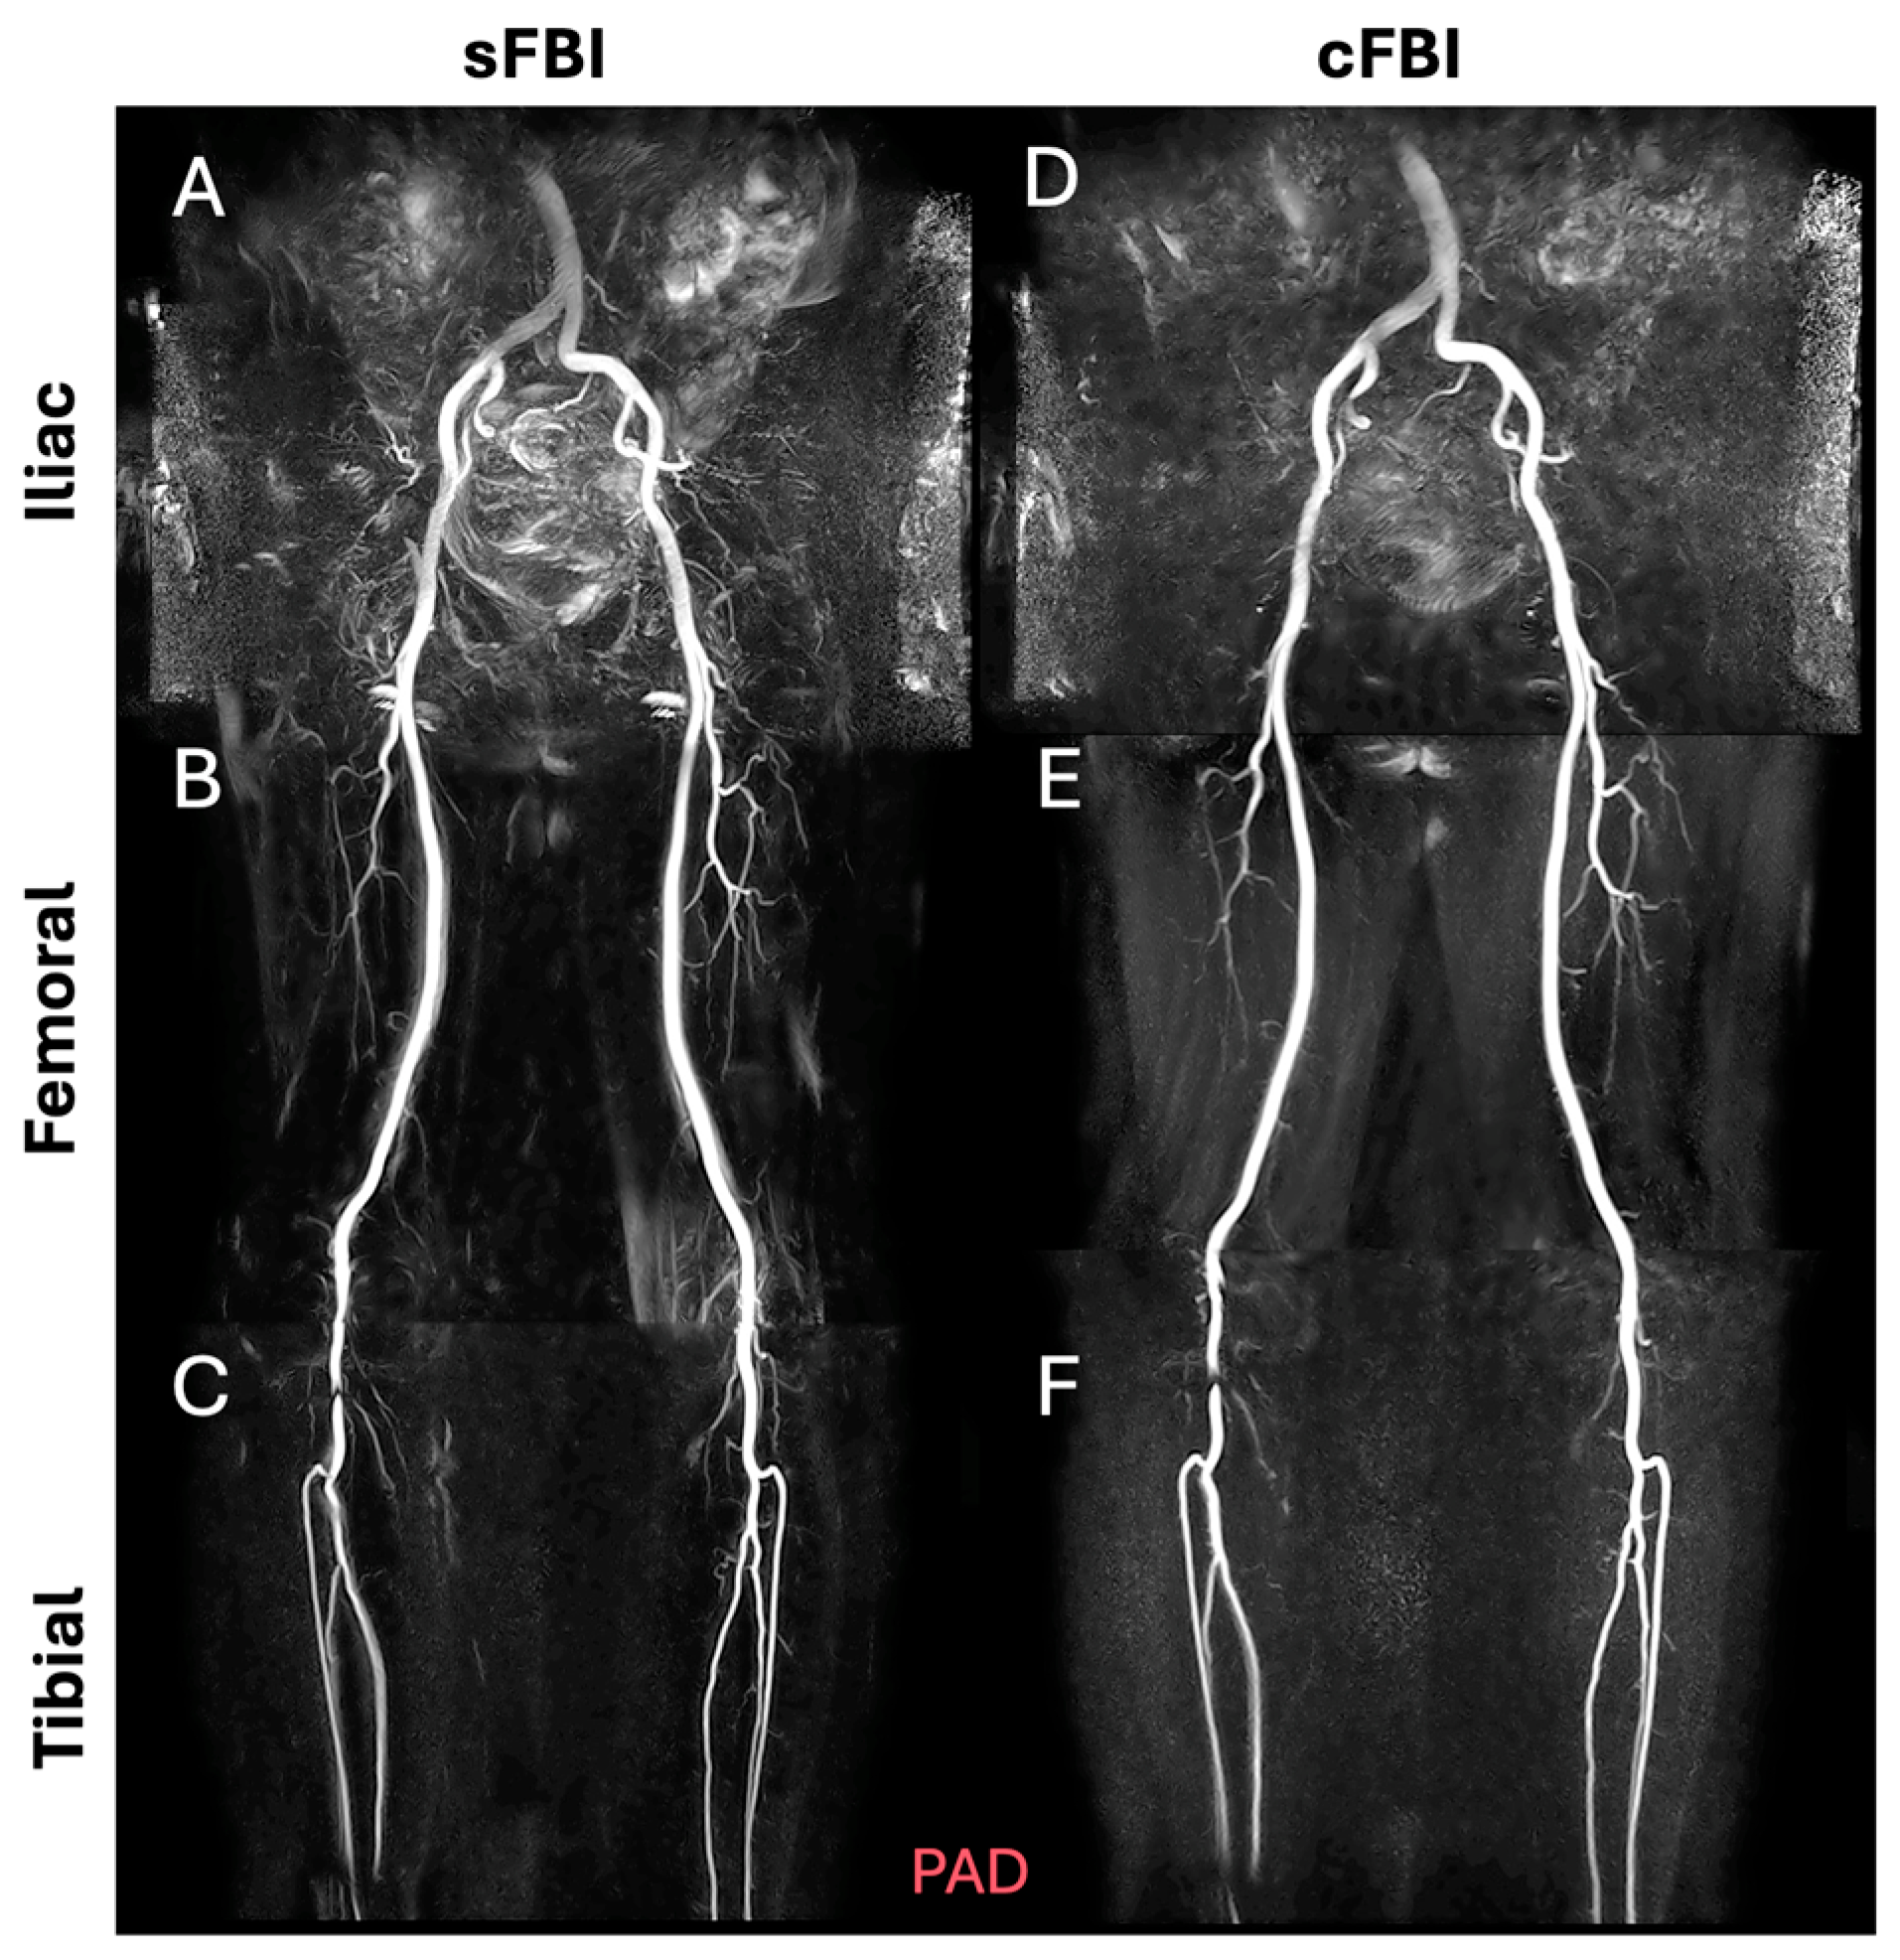

- Malis, V.; Vucevic, D.; Bae, W.C.; Yamamoto, A.; Kassai, Y.; Lane, J.; Hsiao, A.; Nakamura, K.; Miyazaki, M. Fast Non-contrast MR Angiography Using a Zigzag Centric k(y) − k(z) k-space Trajectory and Exponential Refocusing Flip Angles with Restoration of Longitudinal Magnetization. Magn. Reson. Med. Sci. 2025, 24, mp-2023. [Google Scholar] [CrossRef] [PubMed]

- Bae, W.C.; Hahn, L.; Malis, V.; Mesa, A.; Vucevic, D.; Miyazaki, M. Peripheral Non-Contrast MR Angiography Using FBI: Scan Time and T2 Blurring Reduction with 2D Parallel Imaging. J. Imaging 2024, 10, 223. [Google Scholar] [CrossRef] [PubMed]